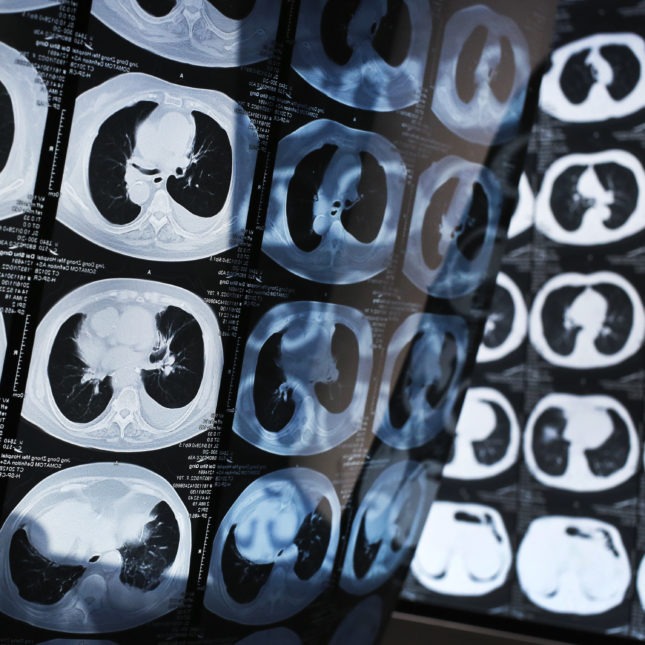

▲肺癌疫苗能激活免疫系统,杀死癌细胞。路透社